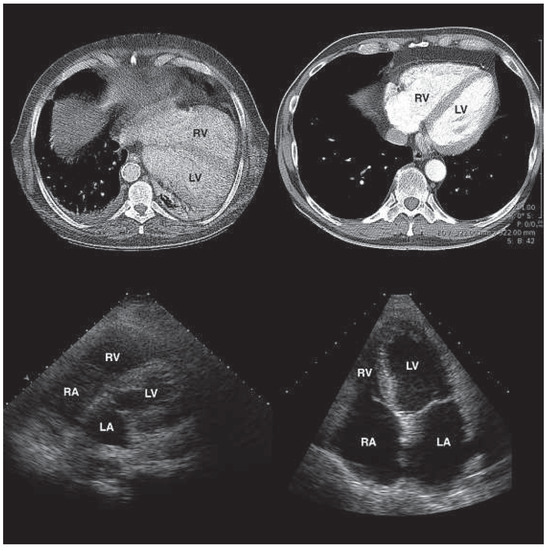

Case Report

Quantification of Differential ECMO Return Flow Through an Axillary Artery Anastomosis Graft with Spectral Doppler Echocardiographyphy

by David G. Platts, Kiran Shekar, Bruce Thomson and John F. Fraser

Venoarterial extracorporeal membrane oxygenation (VA-ECMO) is a specialised form of advanced cardiac life support that can be utilised in critically ill patients who require short term cardiac support. Cardiac imaging, especially with echocardiography, is fundamental to optimal management of patients supported with ECMO. [...] Read more.

Venoarterial extracorporeal membrane oxygenation (VA-ECMO) is a specialised form of advanced cardiac life support that can be utilised in critically ill patients who require short term cardiac support. Cardiac imaging, especially with echocardiography, is fundamental to optimal management of patients supported with ECMO. There are numerous cannulation options available for initiating ECMO. This case report describes the use of a transthoracic echocardiographic transducer and scanner to assess upper limb hyperperfusion in a patient with an axillary artery site for VA-ECMO return flow. The incidence, diagnosis and treatment of this vascular complication of ECMO are discussed. Full article

Figure 1